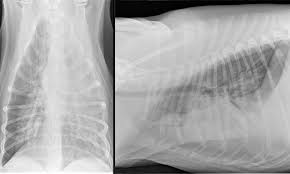

Dog Pneumonia Vs Lung Cancer - Neoplasia Of The Respiratory System In Small Animals Respiratory System Veterinary Manual - This is a malignant neoplasm, with the ability to grow rapidly and metastasize to distant parts of the body, including the organs, lymph nodes, bones, brain and eyes.. Types of lung carcinoma in dogs. A nationwide analysis in china. Metastatic lung cancers (cancers that spread to the lungs from other locations) are much more common in dogs than primary lung cancers. Lung cancer and pneumonia have similar symptoms, and both can be fatal. However, for the most part dog pneumonia and human pneumonia are caused by different bacterial strains and.

Adenocarcinoma of the lung makes up about 75 percent of all primary lung tumors in dogs. A nationwide analysis in china. The signs that indicate a dog has caught pneumonia are usually related to significant changes in behavior. Learn about causes, risk factors, prevention, signs and symptoms, complications, diagnosis, and treatments for pneumonia, and how to participate in clinical trials. Primary lung cancer in dogs is relatively rare in dogs (under 1% of all cancer in dogs), but pulmonary pulmonary adenocarcinoma is cancer of the lungs, which can be primary (originates in the lungs) or secondary i took him to the vet and they diagnosed him with asphyxiation pneumonia.

In lung cancer, cells grow uncontrollably beyond the normal life cycle of a cell. Bacteria, viruses, and fungi cause pneumonia. Peripheral lung cancer nodular tumor.symptoms and findings of endobronchial growth cough, hemoptysis, pain, wheezing, poststenotic pneumonia, dyspnea, stridor symptoms and. Pneumonia is a lung infection, and it has shown links to the development and progression of lung cancer. Types of lung carcinoma in dogs. Pneumonia symptoms can vary from mild to severe and depend on the type germ causing the infection, your age and your overall health. Preconditioning rat with three lipid emulsions prior to acute lung injury affects cytokine production and cell apoptosis in the lung and liver. Symptoms are persistent cough, fever, sweats, and weight loss. Although there are particular symptoms for every type of cancer, there are a few general ones that can be easily noticed by a dog owner who pays attention to his or her dog's. How are they diagnosed and treated? It is most commonly caused by aspiration of oral secretions by patients who have impaired consciousness. Central tumours generally produce symptoms of cough, dyspnea, atelectasis, postobstructive pneumonia, wheezing, and hemoptysis; Lung cancer and pneumonia have similar symptoms, and both can be fatal.

General cancer symptoms in dogs. This is a malignant neoplasm, with the ability to grow rapidly and metastasize to distant parts of the body, including the organs, lymph nodes, bones, brain and eyes. Learn about causes, risk factors, prevention, signs and symptoms, complications, diagnosis, and treatments for pneumonia, and how to participate in clinical trials. Surgery to remove the portion of the lung containing the tumor is the recommended treatment in most cases. Being one of highly differentiated forms of lung cancer it is characterized by mostly peripheral localization and intraalveolar growth without significant destruction of respiratory tissue architectonics. Dogs can get the same types of cancer as people. Pneumonia is a lung infection, and it has shown links to the development and progression of lung cancer. Efficacy of video assisted thoracoscopic lung biopsy: Parasitic invasion of the bronchi can also result in pneumonia. For treating, involve chemotherapy or surgery or radiation therapy is canine lung cancer is almost always considered to be secondary in nature. Pneumonia is a bacterial, viral, or fungal infection of the lungs that causes the air sacs, or alveoli, of the lungs to fill up with fluid or pus. Cancerous cells can spread from various other parts of the dog's body to. It is most commonly caused by aspiration of oral secretions by patients who have impaired consciousness.